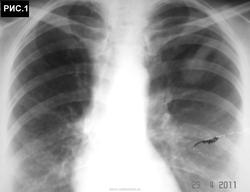

Б-ная 54 г. Живет в небольшом  городе. Поступила в хирургический стационар для холецистэктомии. При ней находился пакет с рентгенограммами органов грудной клетки. Стало известно, что 1 год назад обратилась с бронхолегочными симптомами в поликлинику, где при рентгенографии грудной клетки "выявлено затемнение в легких". После лечения антибиотиками изменения в легких оставались стабильными. Консультирована рентгенологами,онкологами, фтизиатрами, терапевтами, хирургами. Диагноз не установлен. Больная удручена.Хирурги думают. Снимки 6 мес. давности (рис.1,2,3 ).  Рентгенограммы не блеск, но картина везде подобная. Томограмм нет. Ваше слово коллеги! С уважением Nic.

Ответ всегда один - КТ. А без КТ? Не всем дано. В 80% больниц нет КТ. А на боковой я тоже четко не вижу тени. Скорее всего на плевре (передней или задней).

наступил, когда был выполнен последний снимок в отделении. Хорошо видно, что имеется частичное опорожнение ретенционной бронхиальной кисты (рис.4, рис.5). Со слов больной,  незадолго до поступления в стационар имело место отхождение мокроты светлокоричневого цвета без запаха. При анализе выписок из различных учреждений процесс в легких рассматривался как туберкулема легких, туберкулема легких или опухоль, опухоль легкого, патология сосудов легкого, диагноз неясен (овальный фокус затемнения в легком). С уважением Nikolas